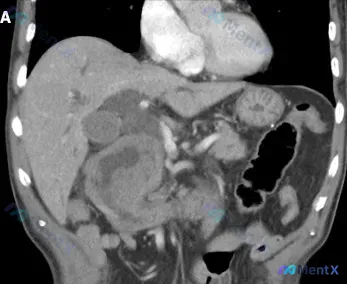

整理到一个腹部CT病例,先放核心影像表现: > 腹部CT:十二指肠降部不均匀增厚,伴 7.6cm × 7.4cm × 7.4cm 低密度肿块,管腔狭窄,肝内外胆管扩张。 补充一些影像分析里的细节: - 病灶形态不规则,边界呈浸润性改变,无完整包膜 - 中心区域有相对低密度的液化/坏死区,周边是中等软...